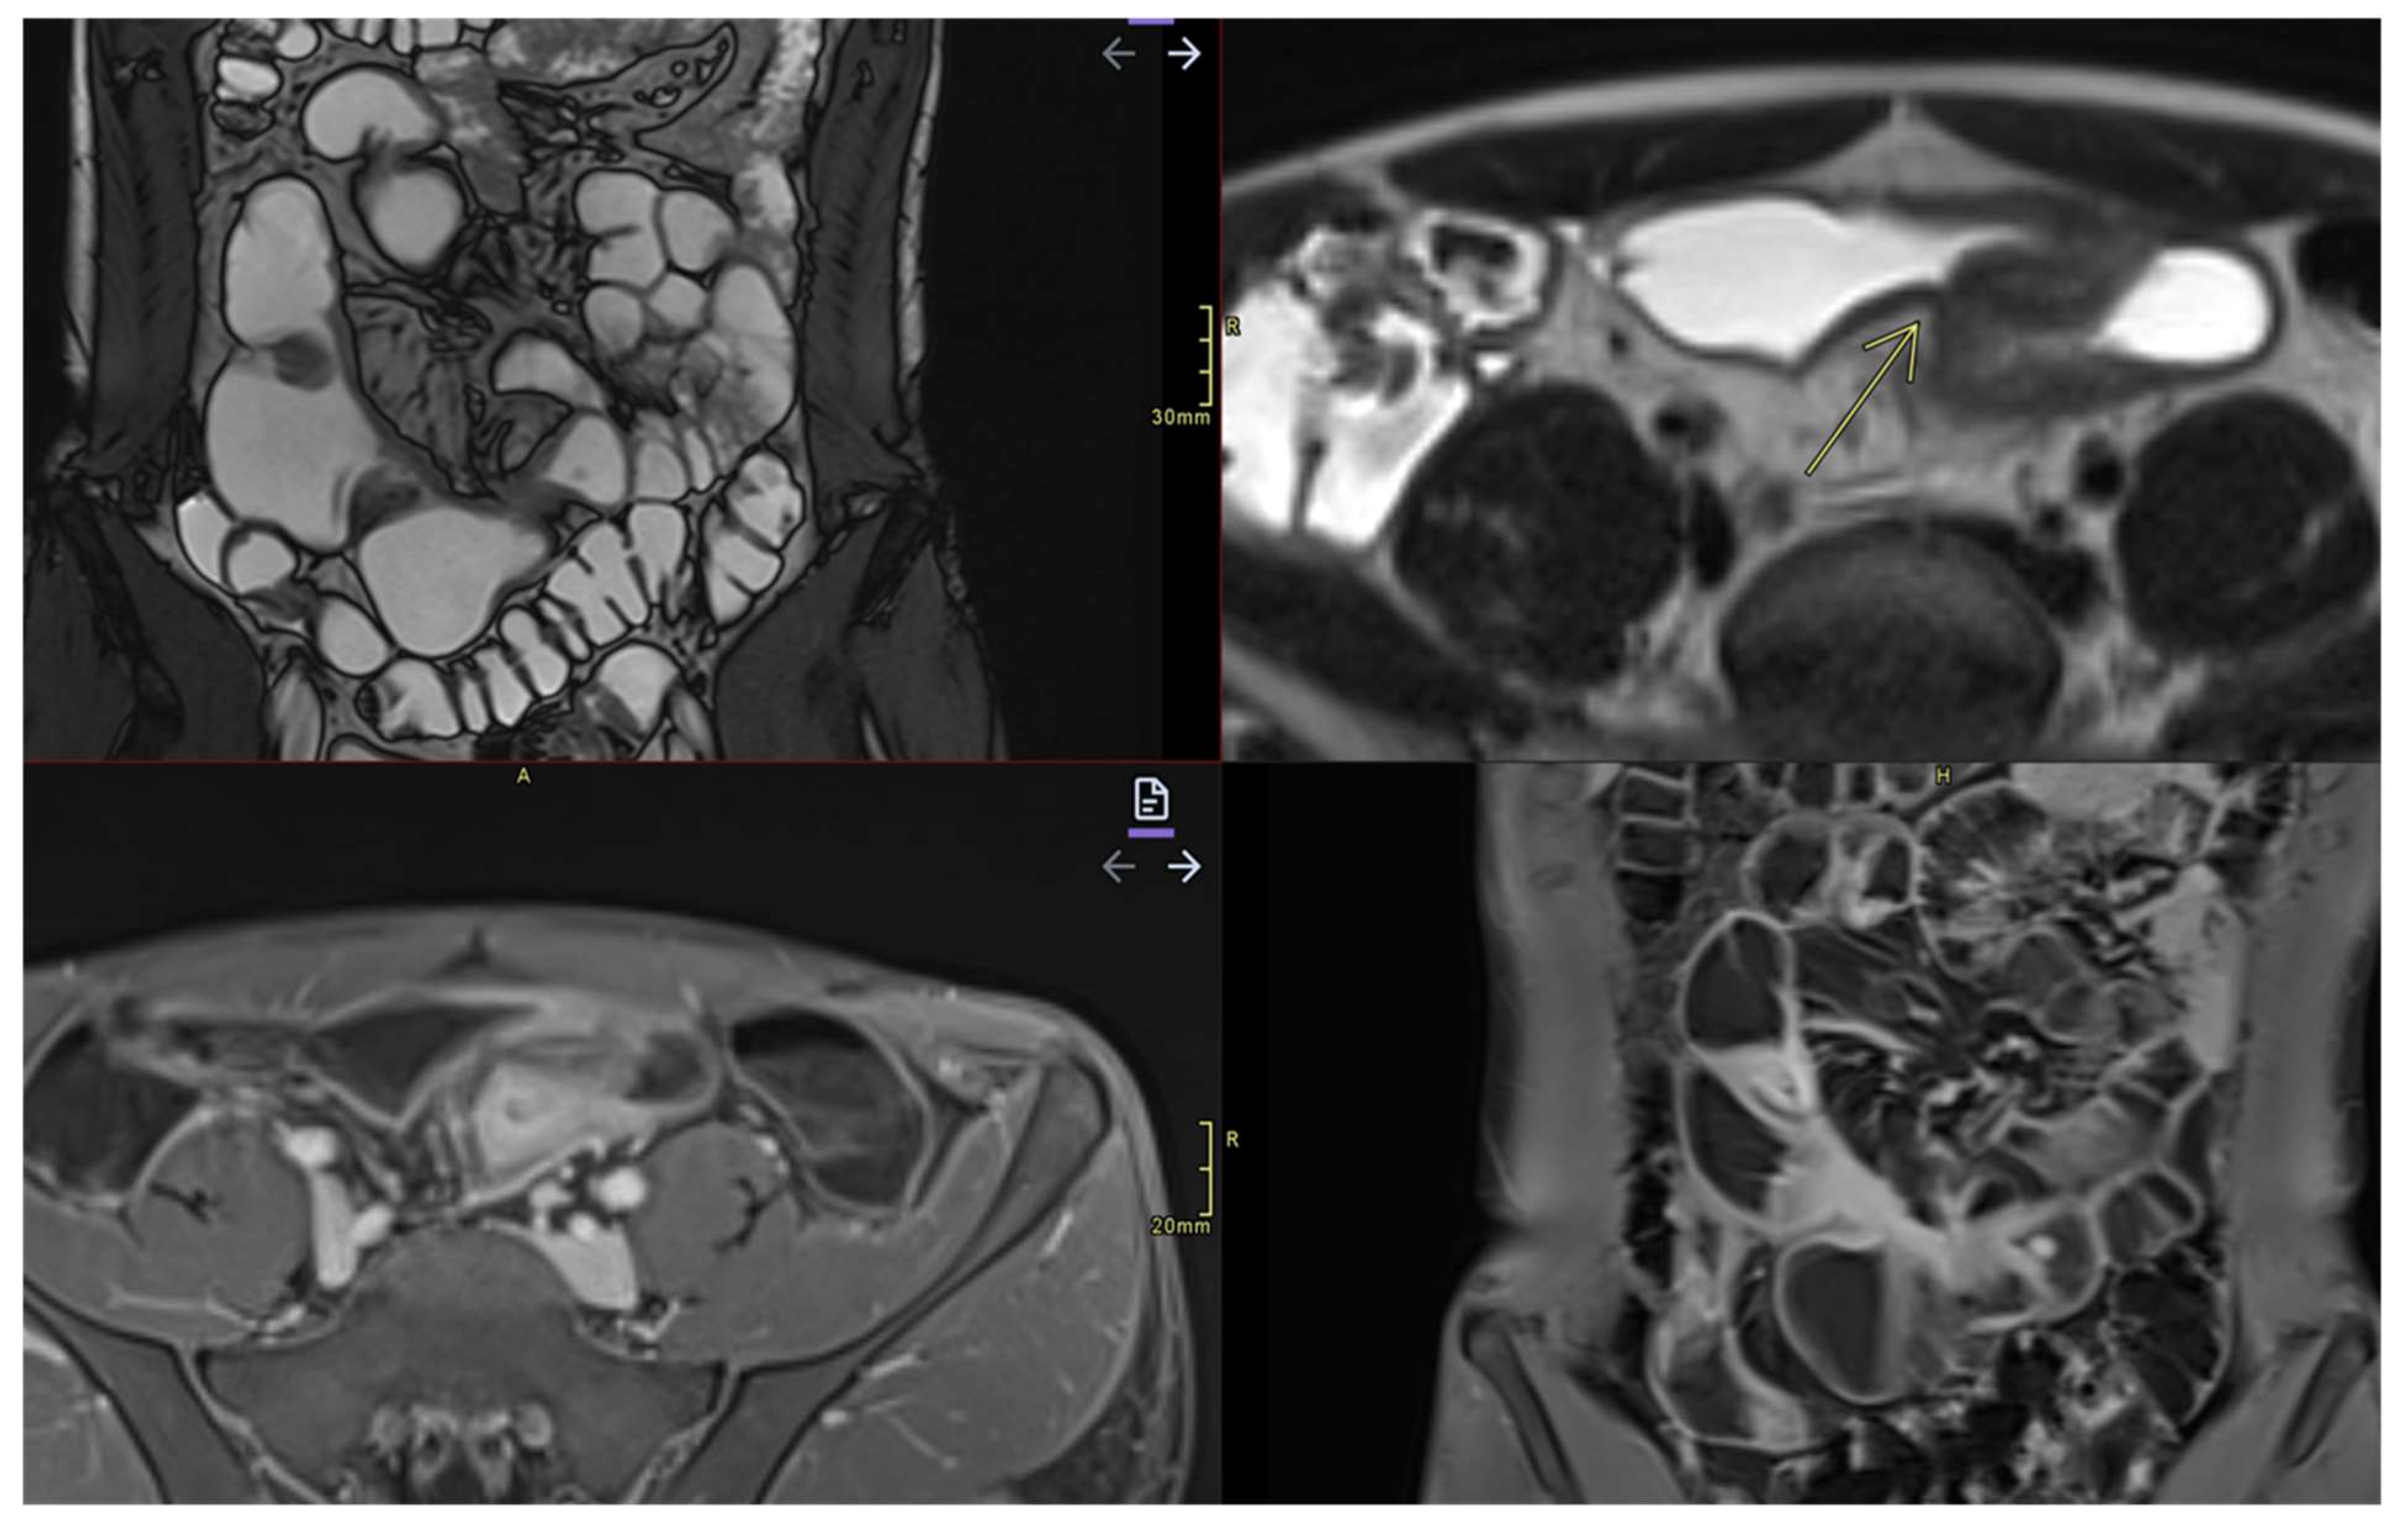

- Fistulas

- They may be enteroenteric, enterocolic, enterovesical, or perianal [8]

- Fistulae occur following advanced penetrating disease [8]

- Abcesses

- Abscesses are found in the abdominal cavity, intestinal wall, or perianal area[8]

- Stenosis

- May be inflammatory (with edema and entrapment) or fibrotic (without inflammatory signs)(Figure 7)

- ➢

- Enteroenteric, enterocutaneous, perianal fistulas: MRE can distinguish between simple and complicated fistulas, guiding the decision between conservative treatment and surgical drainage;

- Intra-abdominal abscesses;

- Fibrous stenosis with dilation of the upstream loops;